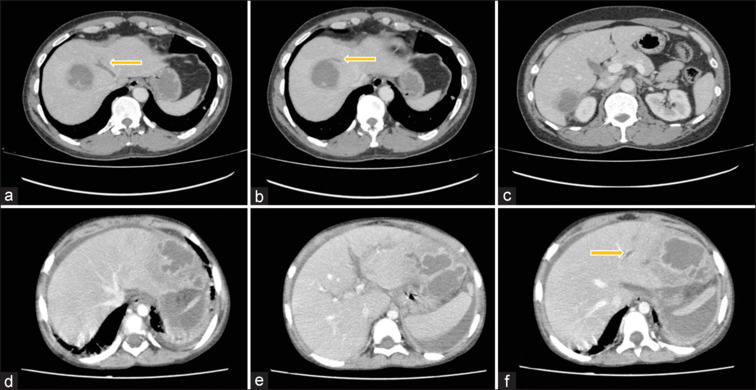

阿米巴病是一种寄生虫感染,阿米巴肝脓肿(ALA)是最常见的肠外表现。ALA的常见并发症包括破裂进入胸膜、心包或腹膜腔。罕见的是,它们会引起血管并发症,如肝静脉和下腔静脉血栓形成,这些静脉可能进一步延伸到右心房或栓塞导致肺血栓栓塞。在本研究中,我们报告了三例ALA患者的血管并发症。血管病变的存在不应错过。通过及时发现和治疗,可以预防血管并发症的发展。

Amebiasis is a parasitic infection with amebic liver abscess (ALA) being the most common extraintestinal manifestation. Common complications of ALA include rupture into the pleural, pericardial, or peritoneal cavity. Uncommonly, they can cause vascular complications such as thrombosis of the hepatic vein and inferior vena cava which may further extend to the right atrium or may embolize resulting in pulmonary thromboembolism. In this study, we report three patients with vascular complications in ALA. The presence of vascular pathology in ALAs should not be missed. With its detection and prompt treatment, the progression of vascular complications can be prevented.